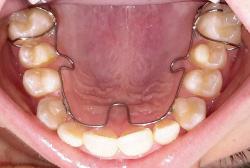

Dr. Brown is highly trained in ALF (Advanced Light Force) therapy. He has over 500 hours in ALF therapy training and has lectured around the world teaching ALF techniques with Dr. Nordstrom, the creator of the ALF appliances. The ALF appliances are thin, conservative appliances that can be used on the upper and lower arches. They hide behind the teeth, are removable and are basically invisible when being worn. This innovative treatment approach is used to address neurological, orthodontic and orthopedic issues, and the benefits are vast. Each appliance is unique to the patient and designed by the doctor to achieve specific goals relating to health, beauty and function. No ALF appliance is the same, and treatment is pain-free.

Airway before ALF Treatment;